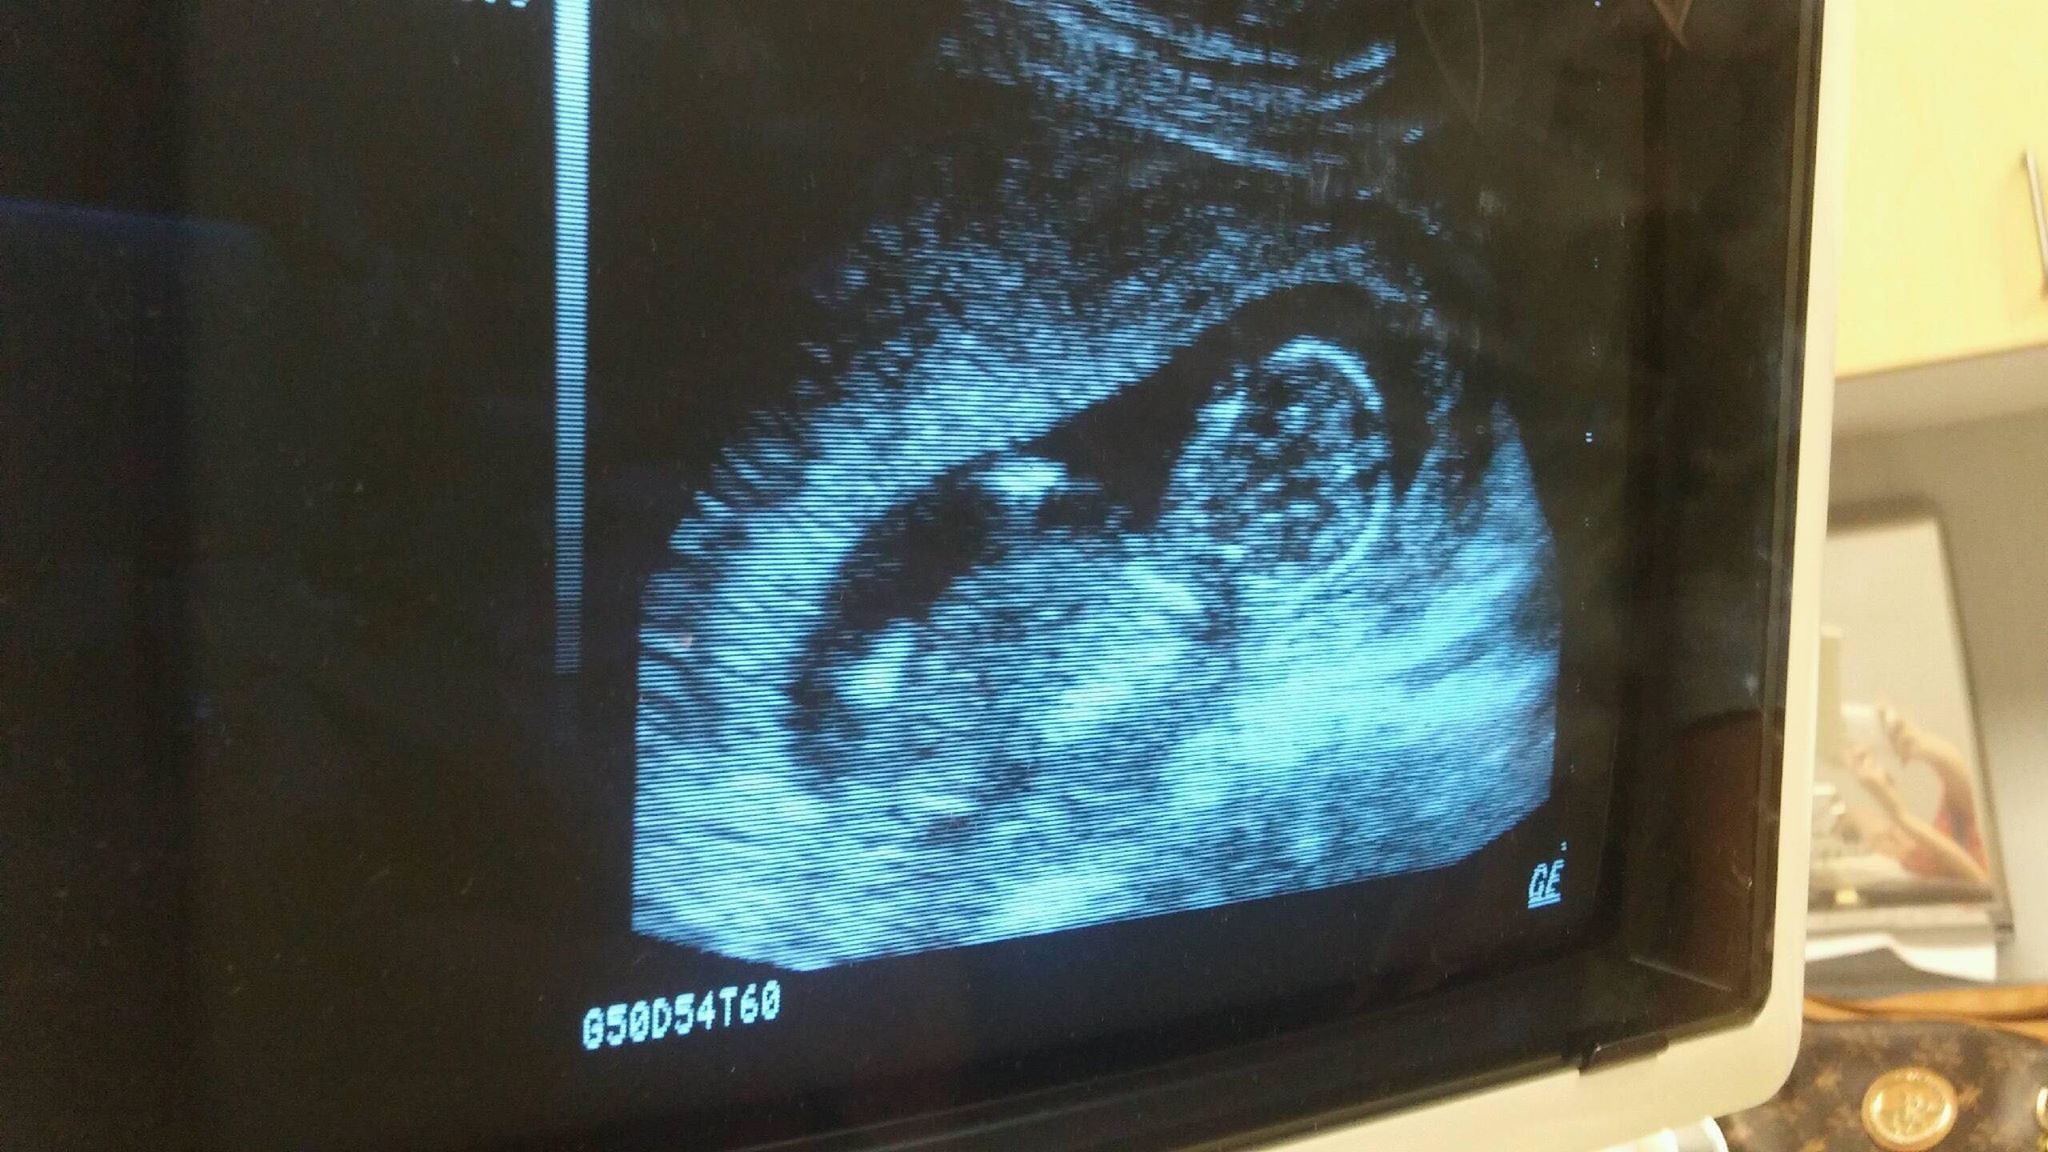

I dont even know what I am looking at lol. Can someone help?! Is there a nub?

This is a forward facing view of baby so no nub visible.

Yeah I see a little ear there on the side of the head! :heart: